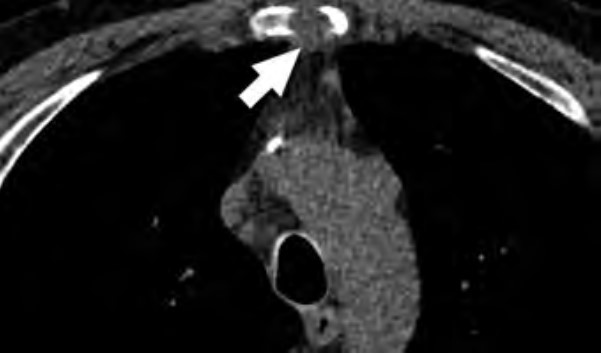

At the individual level, some of the barriers to awareness include unfamiliarity with LCS as a health preventive service tool (Fig. 2), unawareness of the new USPSTF and Centers for Medicare & Medicaid Services (CMS) recommendations for LCS, unfamiliarity with insurance coverage and costs, uncertainty about available accredited LCS programs, lack of culturally appropriate information, and lack of information at an appropriate health literacy level [8–10].

At the individual level, facilitators for LCS are creating patient-centered, culturally tailored educational content to increase interventions to raise awareness and increase health literacy about the new guidelines and fostering non-stigmatizing language and guidelines from national organizations such as the International Association for the Study of Lung Cancer (IASLC) [4, 10, 12, 14]. An effort must be made to inform patients about the importance of early LC detection through LCS, the availability of insurance coverage, and the location of nearby LCS centers using websites such as the “Lung Cancer Screening Locator Tool” [10, 15]. Community health fairs, conventional media, social media, educational brochures, and mailed invitations are examples of how LCS educational information can be disseminated in multiple settings [10]. The educational material can be tailored to focus on hope based on the advancements in LC treatment by including patient testimonials about their experiences with LCS and by tailoring the education to fit the needs and capacities of diverse populations [10, 16]. Online content can provide information and details about LCS programs in multiple languages at the recommended health literacy levels [13]. The Internet and the use of social media can play a key role in the dissemination of information regarding LCS [17]. Prior studies have shown that digital awareness strategies leveraging social media were effective in increasing LCS engagement [17].

At the provider level, unfamiliarity with expanded eligibility criteria and where to refer patients for LCS can be addressed through educational webinars, institutional online resources, and provider-specific educational material that offers continuing medical education credits [18–21]. All these resources will address unfamiliarity with eligibility criteria, skepticism about the benefits of LCS, lack of awareness about LCS insurance coverage, and concerns related to the management of LCS findings [9, 10].

At the community and health care system level, an important facilitator to LCS is updating EMR systems to identify patients who are eligible for LCS under the new guidelines. This information can be incorporated into EMR systems with alerts for eligible high-risk patients, autopopulated referral tools, and lists of certified LCS centers that will help identify eligible patients and promote uptake among diverse patient populations [10, 22]. Online content can facilitate LCS by providing information about LCS programs that is tailored for the local communities served by radiology practices and health care institutions [10, 12]. Furthermore, implementing institutional social media campaigns that emphasize the expanded new eligibility criteria will help overcome knowledge gaps and barriers to awareness [23].